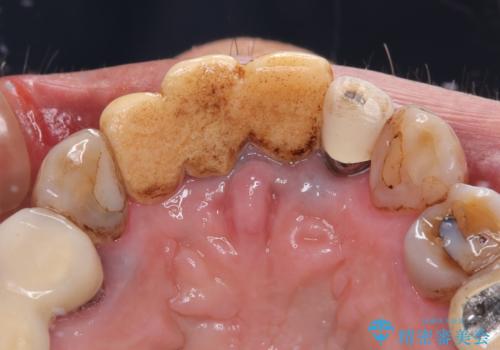

- 治療中の医院で装着した仮歯が汚れていて恥ずかしいとのことで来院された患者様です。

仮歯が不適合で歯肉が腫脹していたため、しっかりと調整した新しい仮歯にして腫れを改善した上で、オールセラミッククラウンにて補綴することとしました。

仮歯の隣の歯も詰め物の範囲が広く、仮歯をセラミックに置き換えても統一感のない口元となってしまうため、相談の結果、前歯6本をオールセラミッククラウンにて補綴治療を行うこととしました。